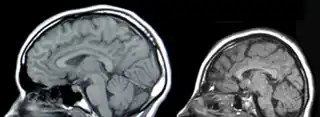

![]() Resonancia Magnética de la Cabeza, Izquierda: Normal, Derecha:Microcefalia. | ||